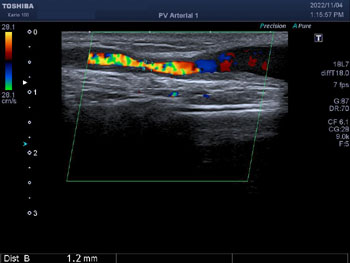

シャントエコー

当院では、透析患者さんのシャント評価を、エコーを用いて定期的に実施しています。また透析前のスタッフのチェックでシャント音やスリルに異常を感じたときはすぐ検査し、必要があればシャント造影→シャントPTAへと治療をすすめます。